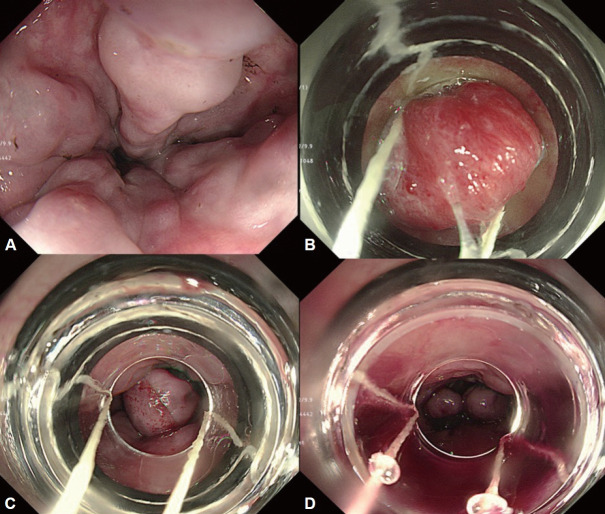

胃食管静脉曲张发生在超过一半的肝硬化患者中,随着肝功能的恶化,发生率增加。尽管随着内窥镜下静脉曲张止血技术的发展以及血管活性药物和预防性抗生素的应用,急性静脉曲张出血的死亡率有所下降,但仍高达20%。因此,对肝硬化患者进行静脉曲张的监测和预防其出血是非常重要的。肝硬化合并门脉高压的患者,应行食管胃十二指肠镜诊断静脉曲张并对其出血风险进行分层。内镜监测间隔根据静脉曲张情况和肝硬化严重程度调整。如果诊断出静脉曲张,则需要一级预防(例如,非选择性β受体阻滞剂或内窥镜预防)来预防静脉曲张出血。急性静脉曲张出血患者应进行适当的治疗,包括及时的内镜止血,并需要二级预防以防止再出血。内镜下静脉曲张结扎是急性食管静脉曲张出血的推荐内镜治疗方法;内镜下静脉曲张梗阻通常推荐用于胃静脉曲张患者。为防止出血,应定期进行内镜监测,直至静脉曲张完全根除,即使静脉曲张消失后也应定期进行内镜随访。在这篇综述中,我们探讨了内镜在胃食管静脉曲张的治疗和管理中的作用。

Gastroesophageal varices occur in more than half of patients with cirrhosis and the incidence increases as liver function worsens. Although the mortality rate for acute variceal bleeding has decreased with the development of variceal endoscopic hemostasis and administration of vasoactive drugs and prophylactic antibiotics, it still reaches 20%. Therefore, surveillance of variceal occurrence and the prevention of their bleeding is very important in patients with cirrhosis. In patients with liver cirrhosis accompanied by portal hypertension, esophagogastroduodenoscopy should be performed to diagnose varices and stratify their bleeding risk. The interval of endoscopic surveillance is adjusted according to variceal condition and cirrhosis severity. If varices are diagnosed, primary prophylaxis (e.g., non-selective beta-blockers or endoscopic prophylaxis) is required to prevent variceal bleeding. Appropriate treatment, including timely endoscopic hemostasis, should be performed in patients with acute variceal bleeding, and secondary prophylaxis is required to prevent rebleeding. Endoscopic variceal ligation is the recommended endoscopic treatment for acute esophageal variceal bleeding; endoscopic variceal obstruction is usually recommended in patients with gastric varices. To prevent bleeding, endoscopic surveillance should be performed at regular intervals until the varices have been eradicated, and endoscopic followup should be performed periodically even after their disappearance. In this review, we investigate the role of endoscopy in the treatment and management of gastroesophageal varices.